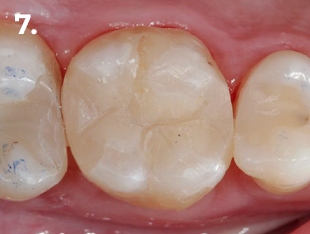

Nell’immagine clinica e radiografica finale si osservano corretti profili anatomici, con adeguata convessità e punti di contatto funzionali.

Fig. 1 Immagine clinica iniziale

Fig. 7 Immagine clinica finale

La rigidità del sistema di matrici HALO™ ha assicurato un’elevata stabilità, permettendo di mantenere la matrice in posizione anche su margini profondi, semplificando notevolmente la procedura restaurativa e garantendo un corretto punto di contatto.